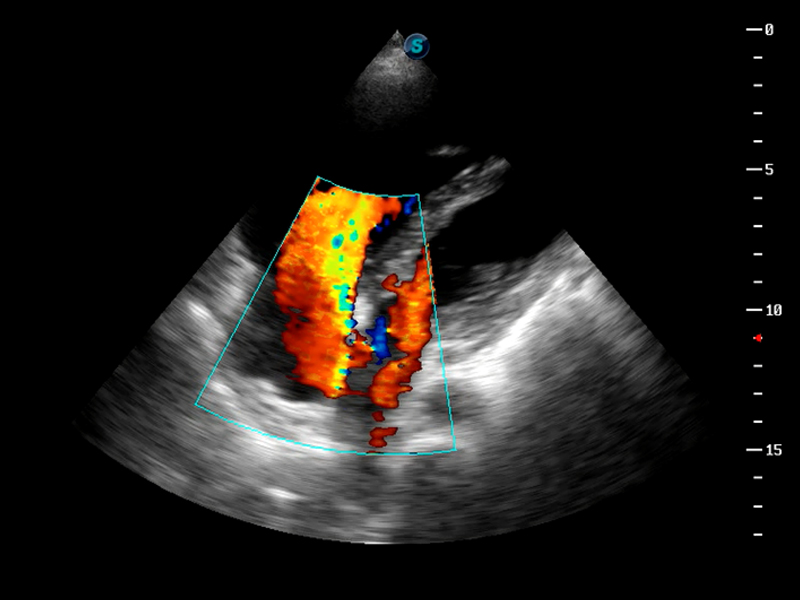

S9便携式彩色多普勒超声诊断仪是米兰官方网站研发的高端便携彩超设备,外观设计新颖、产品性能卓越。S9在便携超声领域采用了突破传统的触摸屏交互设计,并以先进的软件硬件技术和设计理念,为您带来清晰的图像质量、稳定的工作性能和便捷的操作体验。

AutoC智能血流追踪